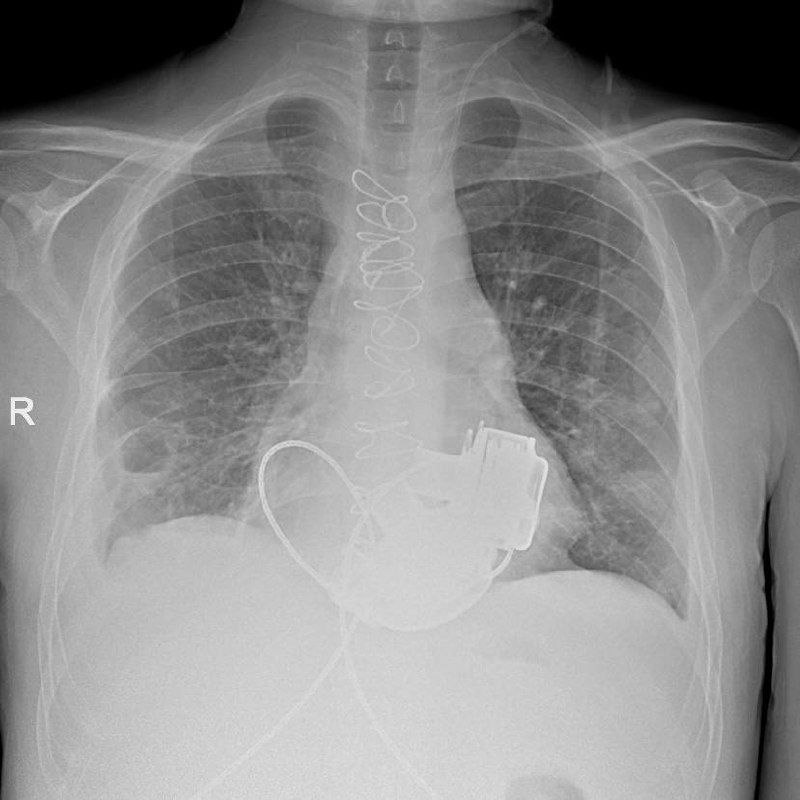

В конце ноября 2025 года ему впервые в России имплантировали сразу два искусственных желудочка сердца.

Имплантация искусственных желудочков — мостик к пересадке сердца, так как позволяет пациенту дожить до спасительной операции, уточнили в комитете здравоохранения Петербурга.